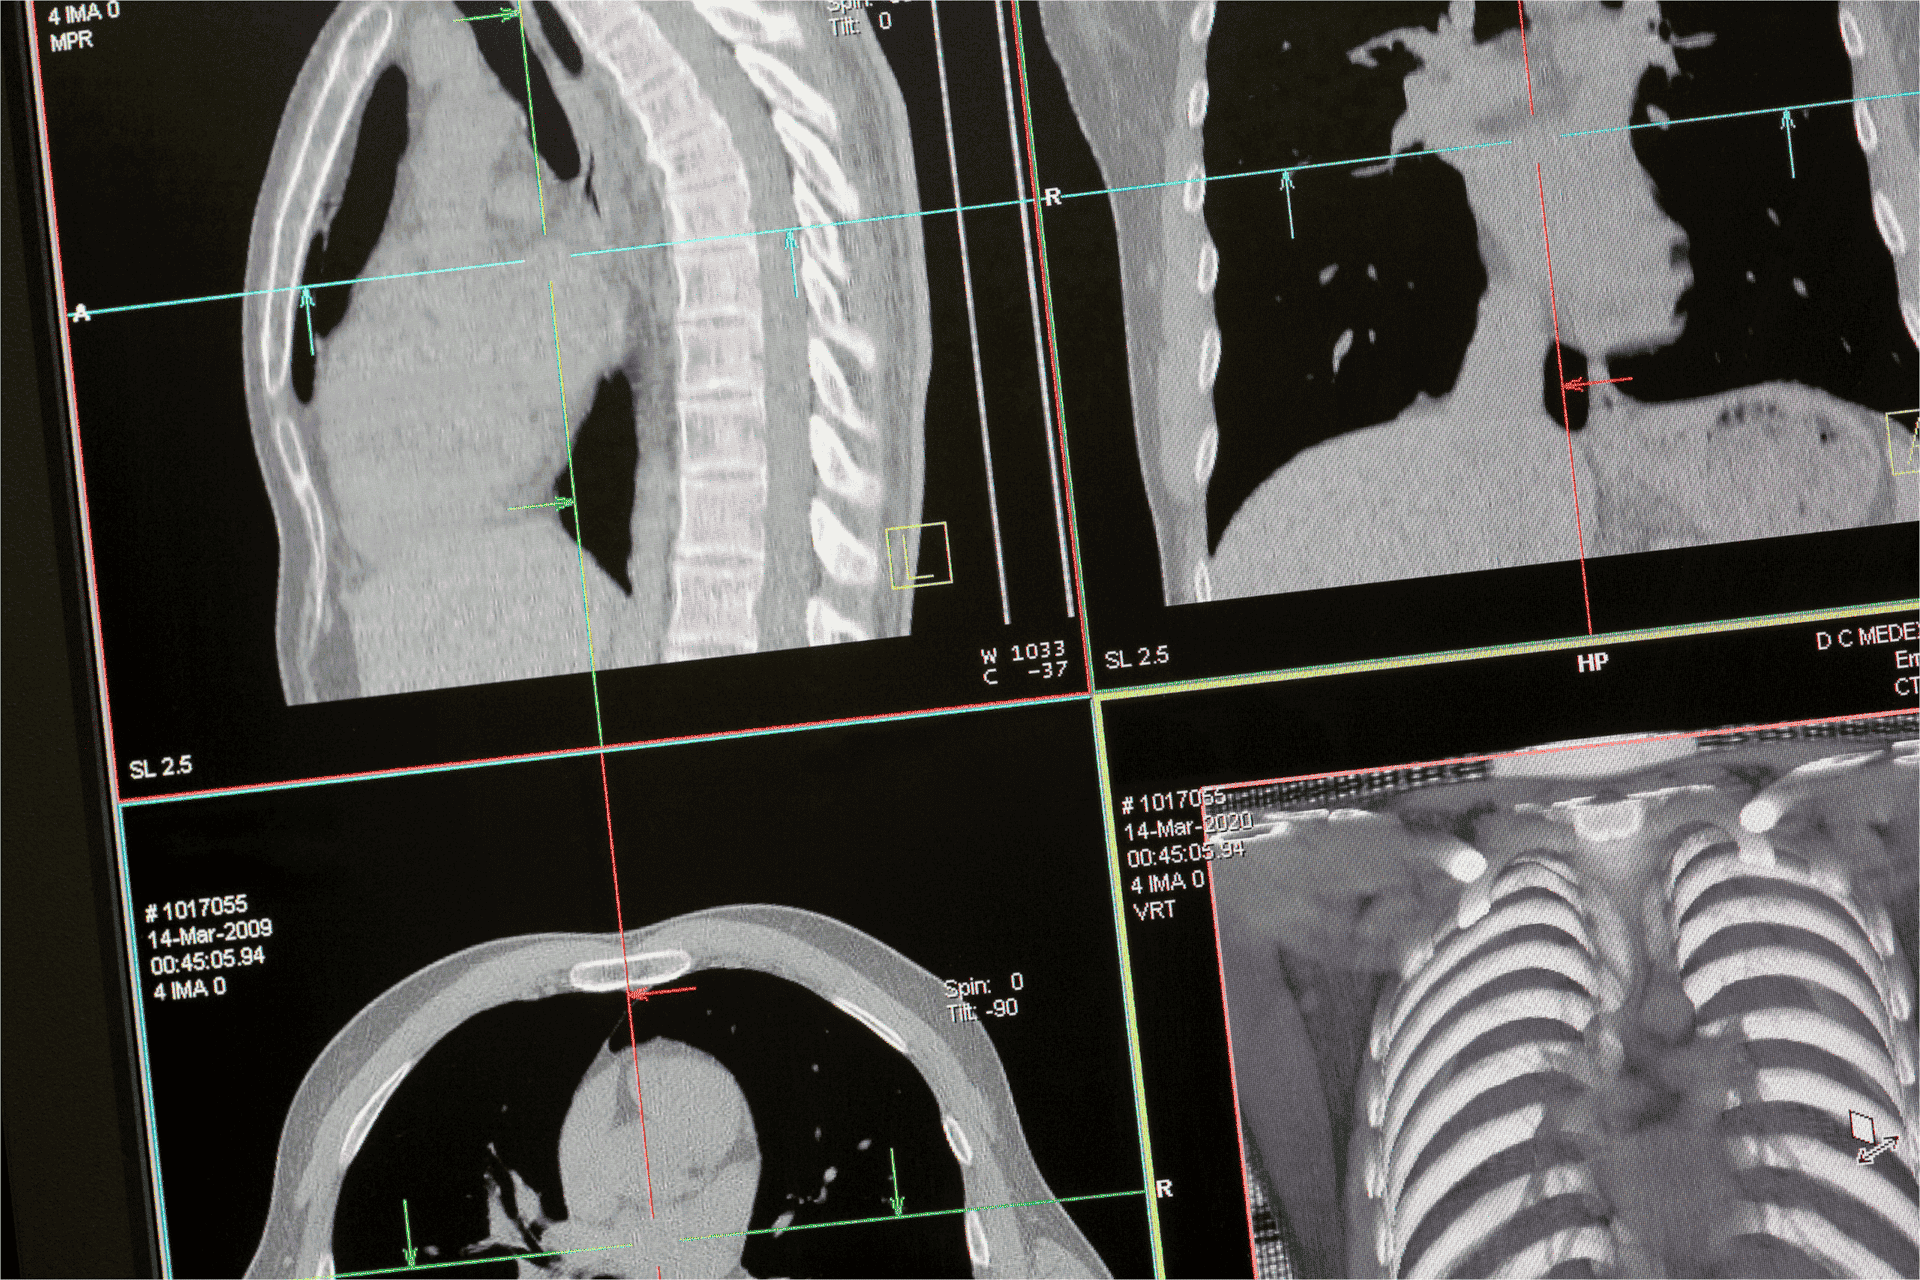

AI’s integration into diagnostic imaging extends beyond MRIs. As algorithms become more sophisticated, AI’s role in interpreting other medical images, such as CT scans and X-rays, is also expanding. This cross-modality capability further amplifies AI’s utility in diagnostic radiology, offering clinicians a unified platform for diverse image analysis.